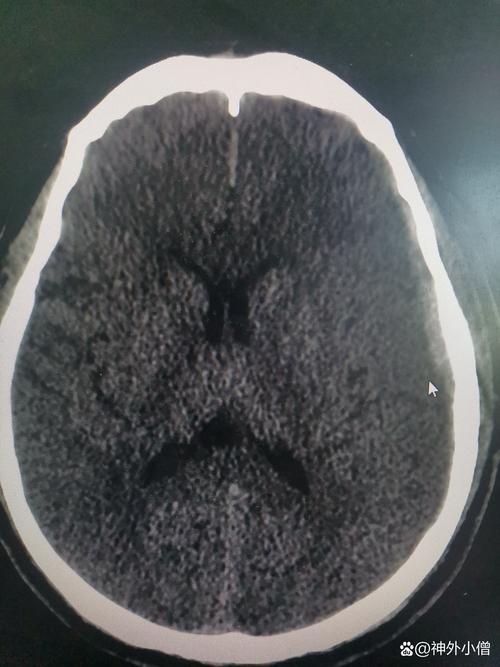

脑梗死 (Cerebral Infarction / Stroke)

(图片来源网络,侵删)- 俗称“中风”,指因脑部血管堵塞,导致局部脑组织因缺血、缺氧而发生坏死。

- CT扫描:

- 早期(6小时内)可能看不出明显异常,或者仅见密度轻微降低。

- 24-48小时后,梗死区域和周围的水肿带会表现为低密度区域,边界不清,像一个“模糊的阴影”。